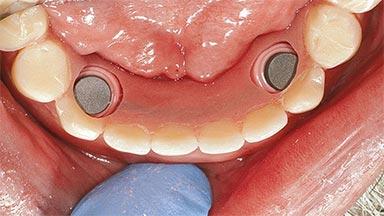

An 83-year-old man presented together with his caregiver at the dental department of the Medical University of Innsbruck, Austria with complaints of swelling in the right maxillary canine area and loss of retention of his 5-years-old mandibular denture. The patient had a significant medical history (20 years) of bipolar affective disorder with moderate depression (F 31.3) and dementia in Alzheimer’s disease (F 00.2). The patient had been in ambulant psychiatric therapy for his depressive illness for the past 20 years. He lived alone and had no children; his sister assisted with daily living. She reported that the patient exhibited compulsive hoarding behavior. In the previous two months, she had noted increasing disorientation and vertigo in the patient. She therefore accompanied him for a medical consultation at the Department of Psychiatry and Psychotherapy of the Medical University of Innsbruck. He was released home after a 6-week inpatient stay.

# of Implants 2

Type of Implants One-Piece

Attachment One-Piece

Prosthesis Type RDP